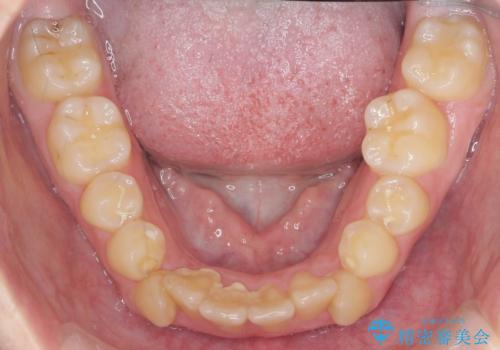

歯並びのせいで歯ブラシがしづらい マルチブラケットを用いた抜歯矯正

- 歯並びのがたつきにより歯ブラシがしづらく、今後虫歯になってしまう不安から、矯正治療を希望されて来院されました。

歯を並べるにはスペースが不足しているため、小臼歯の抜歯を4本行うマルチブラケット矯正による治療を計画します。